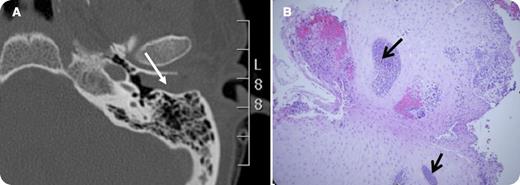

A 37-year-old woman received an allogeneic hematopoietic cell transplantation for acute promyelocytic leukemia (APL) in second complete molecular remission. She had previously received cytotoxic chemotherapy, tretinoin (ATRA), and arsenic trioxide. She presented with acute left-side hearing loss, tinnitus, and fullness. A complete blood count with peripheral smear was unremarkable. Otoscopy revealed a pale granular mass obstructing the left external auditory canal without inflammation or purulent discharge. A computed tomography scan showed that the left external auditory canal was completely occluded by a nonspecific soft tissue density (Panel A; white arrow) with no erosive osseous changes. Cultures (aerobic and anaerobic bacteria, acid-fast bacilli, fungi) were negative. Tissue biopsy of the external ear mass revealed squamous epithelium along with multifocal areas of abnormal, monomorphic cells (Panel B; black arrows; hematoxylin and eosin stain; magnification ×10) consistent with a myeloid sarcoma. Special stains (not shown) indicated that these cells were of myeloid hematopoietic lineage. Immunohistochemistry confirmed their myeloid origin (CD45+, MPO+, and CD117+). Peripheral blood was positive for the PML-RARA fusion gene. She soon developed lethal APL progression with coagulopathy.

The frequency of extramedullary relapse in APL may be increasing. This is thought to correspond with the introduction of ATRA as a component of APL therapy. ATRA stimulates expression of adhesion molecules on both APL cells and keratinocytes, potentially increasing tropism of APL cells to the skin where they proliferate.